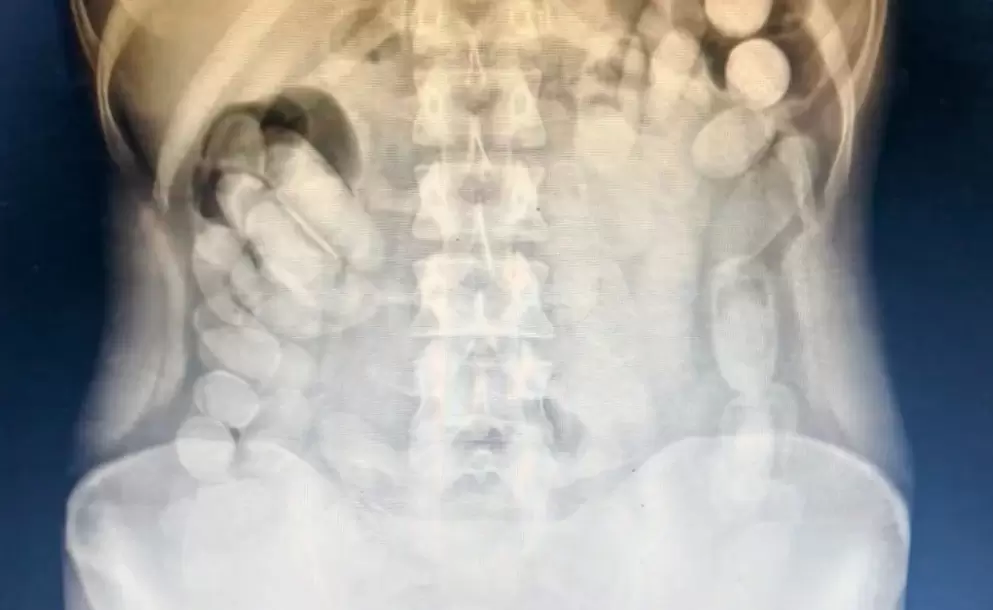

Pero lo peor estaba por revelarse: al ser interrogada, la mujer confesó que había ingerido muchas más. Su cuerpo era, literalmente, una bomba de tiempo. Inmediatamente, el Juzgado Federal Nº 2 de Tucumán ordenó su traslado al Centro de Salud de la capital provincial. La prioridad dejó de ser el delito: se trataba ahora de salvarle la vida. En el nosocomio, una radiografía confirmó el horror: decenas de envoltorios alojados en su abdomen, con el riesgo latente de que alguno se rompiera y provocara una intoxicación letal. La mujer, transformada en "mula humana", ingresó en observación médica estricta.

Horas más tarde, logró evacuar 106 cápsulas adicionales. Sumadas a las 12 incautadas inicialmente, el total alcanzó las 118. El análisis posterior con Narcotest arrojó un resultado contundente: cocaína. El peso final de la sustancia secuestrada fue de 1 kilo 388 gramos. La mujer quedó detenida por orden del magistrado interviniente. Pero, más allá del delito, el caso dejó al descubierto el costado más crudo y peligroso del narcotráfico: el uso de cuerpos humanos como contenedores, la deshumanización, la desesperación y el altísimo riesgo de muerte que asumen muchas veces personas vulnerables en busca de un ingreso.